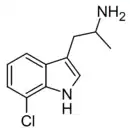

α-Alkyltryptamines are a group of substituted tryptamines which possess an alkyl group, such as a methyl or ethyl group, attached at the alpha carbon, and in most cases no substitution on the amine nitrogen.[17][18][19] α-Alkylation of tryptamine makes it much more metabolically stable and resistant to degradation by monoamine oxidase, resulting in increased potency and greatly lengthened half-life.[19] This is analogous to α-methylation of phenethylamine into amphetamine.[19]

Many α-alkyltryptamines are drugs, acting as monoamine releasing agents, non-selective serotonin receptor agonists, and/or monoamine oxidase inhibitors,[20][21][22][23] and produce psychostimulant, entactogen, and/or psychedelic effects.[17][18][19] The most well-known of these agents are α-methyltryptamine (αMT) and α-ethyltryptamine (αET), both of which were used clinically as antidepressants for a brief period of time in the past and are abused as recreational drugs.[18][19] In accordance with its action as a dual releasing agent of serotonin and dopamine, αET has been found to produce serotonergic neurotoxicity similarly to amphetamines like MDMA and PCA, and the same is also likely to hold true for other serotonin and dopamine-releasing α-alkyltryptamines such as αMT, 5-MeO-αMT, and various others.[24]

5-Chloro-αMT | 1-(5-Chloro-1H-indol-3-yl)propan-2-amine | 712-07-2 |

7-Chloro-AMT | 1-(7-chloro-1H-indol-3-yl)propan-2-amine | 711-99-9 |